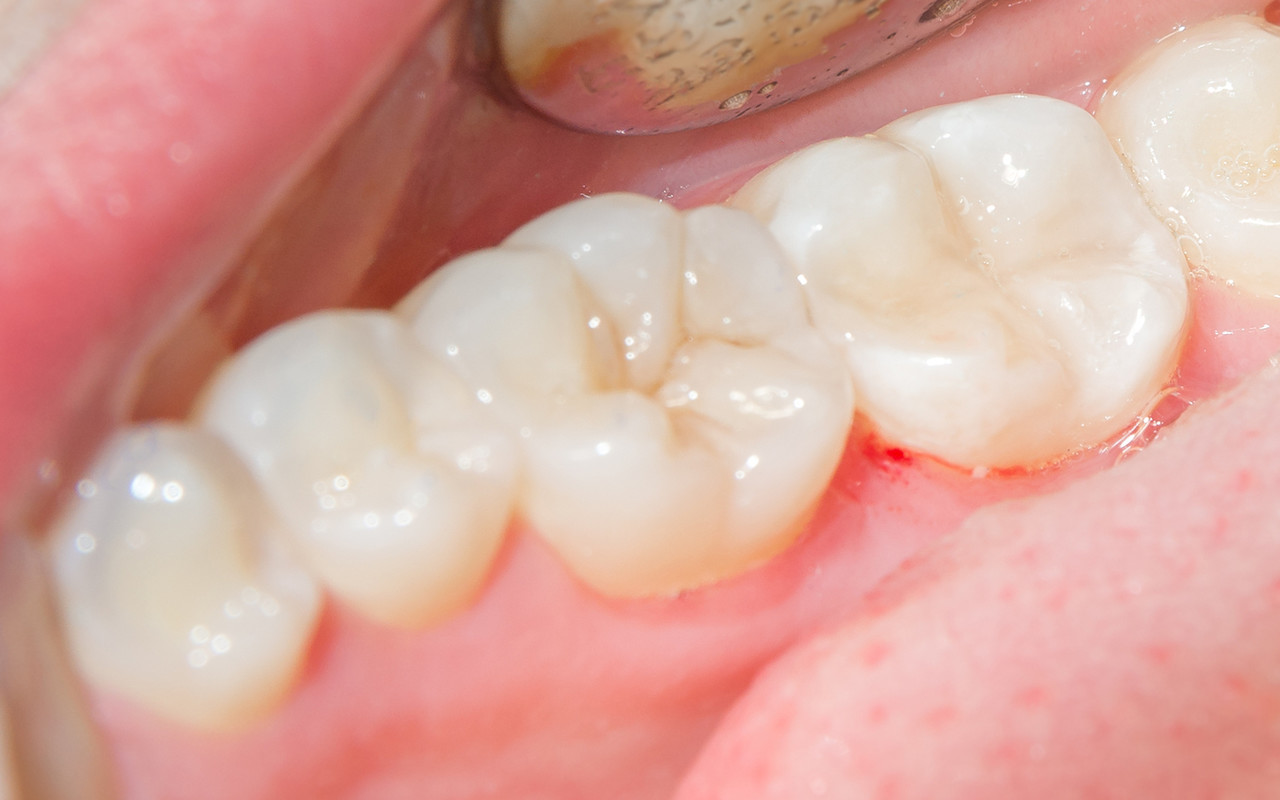

닥터조치과 치료사례

DR. CHO DENTAL CLINIC

본 이미지는 환자의 동의를 얻어, 동일 환경에서

촬영하였습니다. 시술, 수술 후에는 개인에 따라 출혈, 염증,

감염 등 부작용이 발생할 가능성이 있으므로 세심한 주의가

필요합니다. 의료진과 상담 후 결정하시기 바랍니다.

닥터조치과에서 치료받으신 분들의 치료사례 전후사진입니다.

본 이미지는 환자의 동의를 얻어, 동일 환경에서 촬영하였습니다. 시술, 수술 후에는 개인에 따라 출혈, 염증, 감염 등 부작용이 발생할 가능성이 있으므로 세심한 주의가 필요합니다.

의료진과 상담 후 결정하시기 바랍니다.